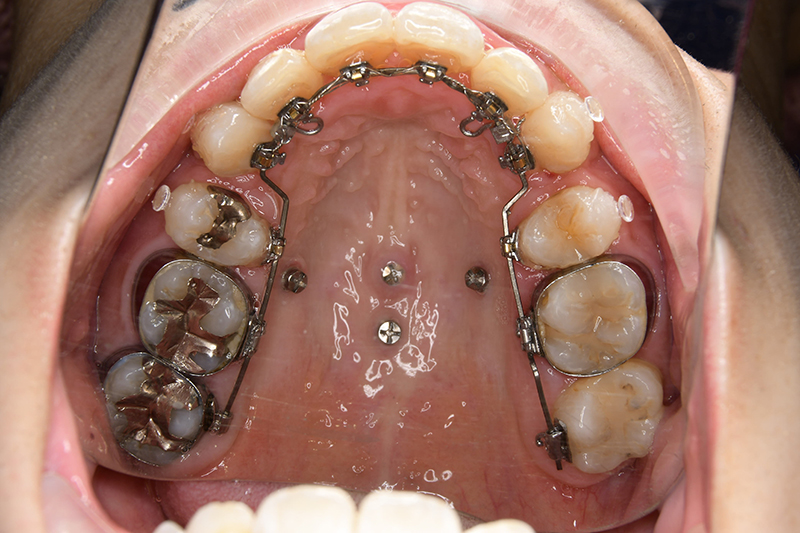

使用装置 上顎 : Clippy L

下顎 : 0.018" × 0.025" standard edgewise

その他装置 TAD(インプラントアンカー)

口腔内ゴムの使用 12ヵ月

批評・予后 上顎前歯の可及的な後退と臼歯関係のⅡ級を保つためにアンカレッジコントロールはmaximumとしTADを使用してスライディングメカニクスにて前歯遠心移動を行った。また下顎はリンガルからのアプローチであったためその特性を生かし、臼歯のアップライトを速やかに達成して左下5の配列も予定通り行えた。また大幅な前歯の後退に伴い、軟組織の大幅な改善が認められたように思う。